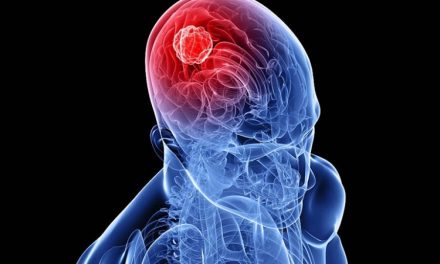

La inteligencia aumentada se enfoca en el papel de asistencia de la IA, reconociendo que la medicina es fundamentalmente una profesión humana que se beneficia enormemente de la asistencia tecnológica. Un radiólogo que utiliza IA para detectar tumores microscópicos que podrían pasar desapercibidos al ojo humano no está siendo reemplazado por la tecnología; está siendo potenciado por ella [6].

Los dispositivos médicos con IA aprobados por la FDA abarcan múltiples especialidades. La radiología lidera con la mayoría de aplicaciones, seguida por cardiología con 161 aprobaciones [12]. Estos sistemas pueden detectar anomalías en imágenes médicas con una precisión que frecuentemente supera la de especialistas experimentados, identificar patrones en electrocardiogramas que predicen eventos cardíacos, y analizar datos de laboratorio para sugerir diagnósticos que podrían pasar desapercibidos.

Un cardiólogo que no utiliza algoritmos de IA para analizar electrocardiogramas está dejando de lado una herramienta que podría detectar arritmias peligrosas con mayor precisión. Un radiólogo que no emplea sistemas de IA para revisar mamografías está perdiendo la oportunidad de detectar cánceres en etapas más tempranas.